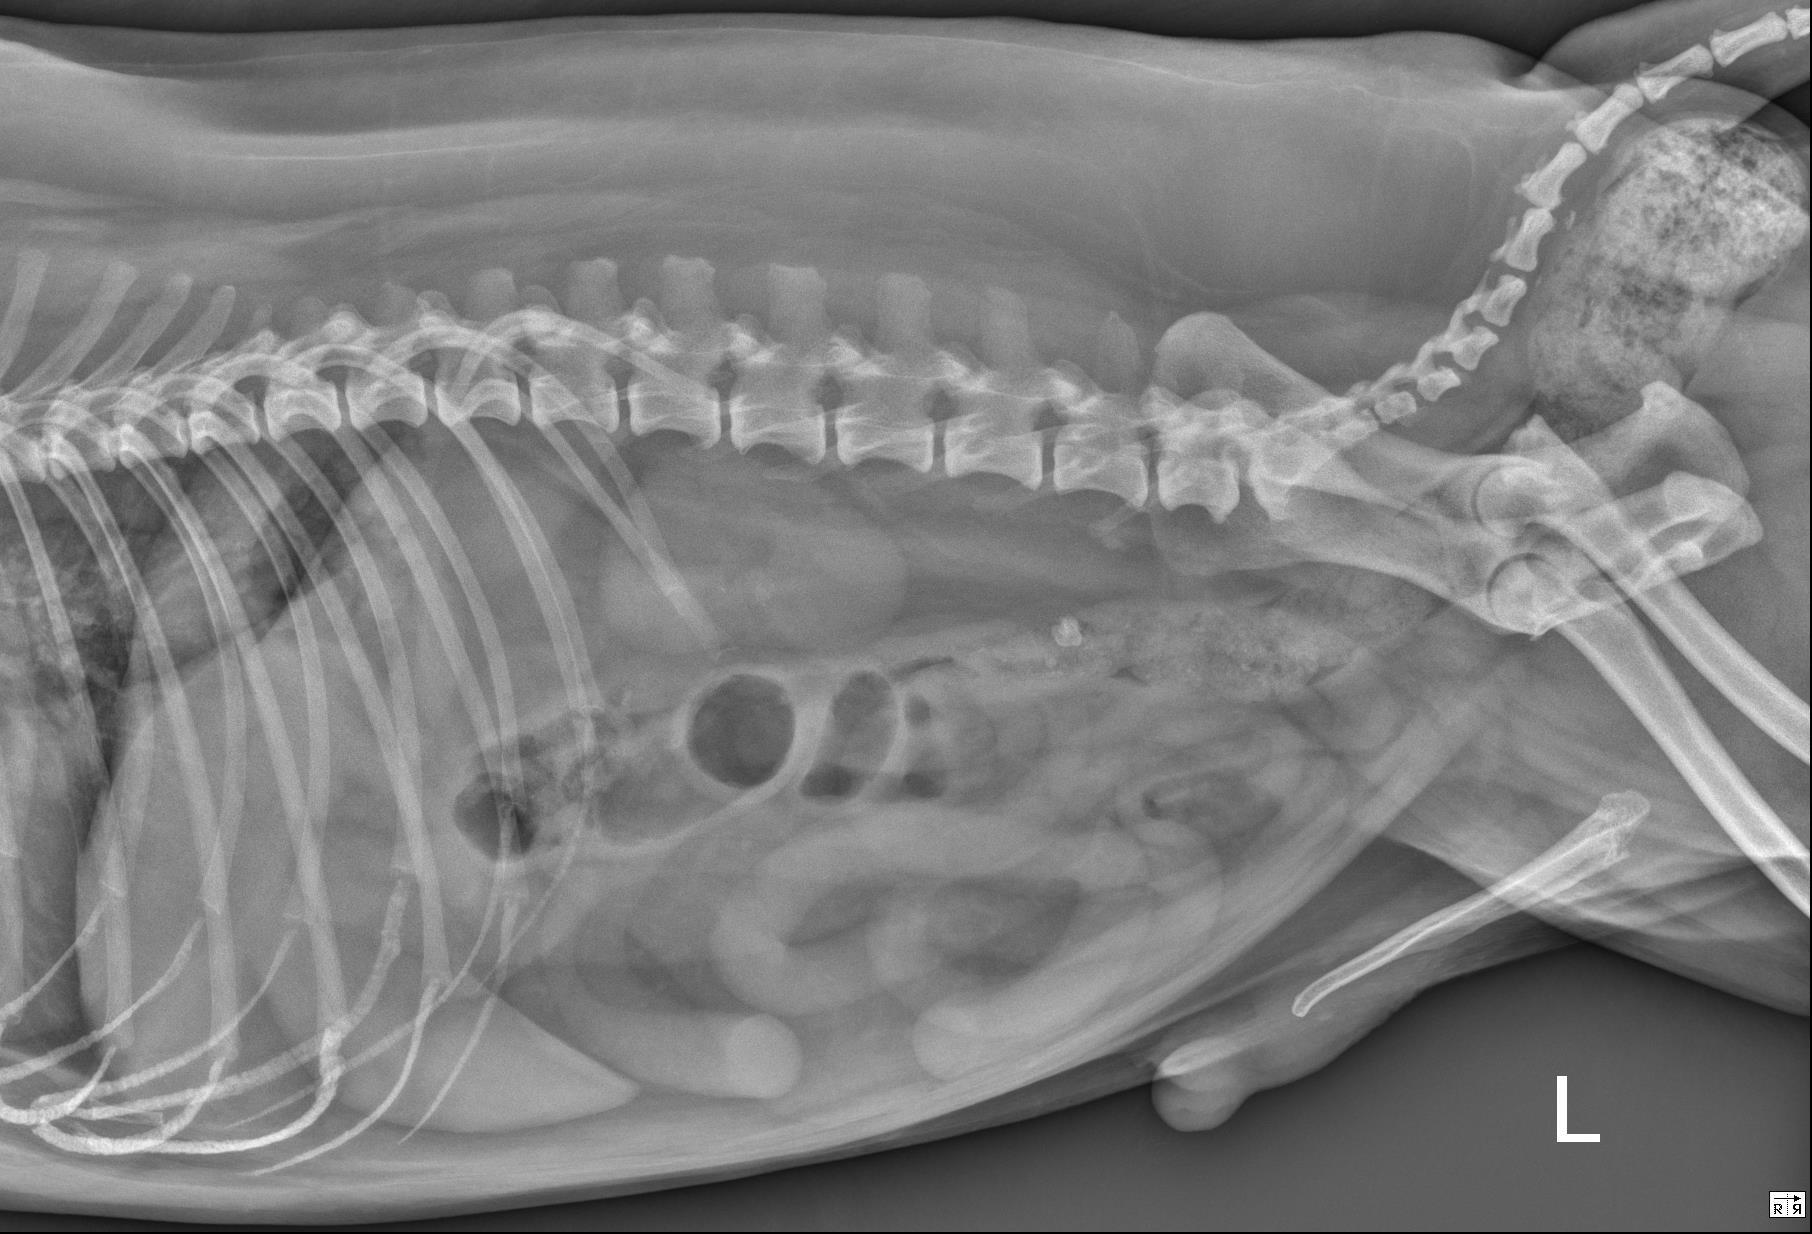

5犬猫小肠机械性梗阻的X光片诊断